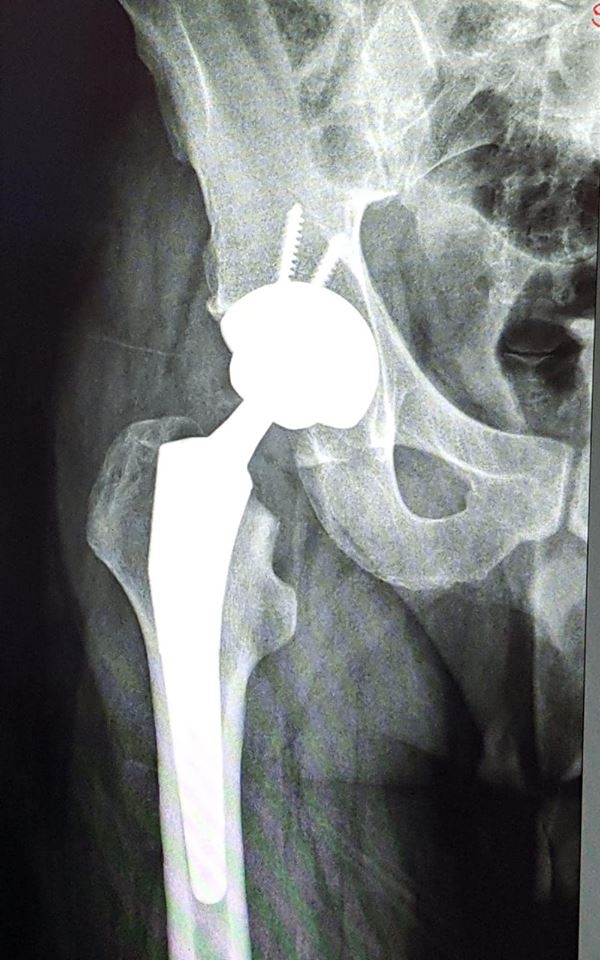

”Investițiile realizate și echipamentele achiziționate în ultima perioadă, au făcut posibilă o nouă premieră medicală pentru Spitalul Județean de Urgență Bistrița. O echipă mixtă, coordonată de Dr. Remus Opriș – medic primar Ortopedie și Traumatologie, șef lucrări în cadrul UMF Târgu Mureș și Dr. Bogdan Bumbu – medic primar Ortopedie și Traumatologie, șef secție, a realizat prima artroplastie totală de șold, utilizând o endoproteză totală necimentată, cuplu ceramică-ceramică. Pacientul a fost un tânăr diagnosticat cu coxartroză secundară NACF, stadiul V. STEINBERG. Din echipa operatorie au mai făcut parte: Dr. Florin Cioancă – medic specialist Ortopedie și Traumatologie, Dr. Alexei Russu – medic primar ATI, As. Monica Murza – instrumentar. Succes în continuare!” a fost mesajul postat de Gabriel Lazany, managerul Spitalului, pe pagina sa de Facebook.